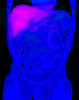

Expected Label Value (ELV) Computation for Multi-Atlas Image Soft-Segmentation

This is the public Matlab implementation for medical image soft-segmentation using the atlas-based expected label value (ELV) approach proposed by Aganj and Fischl (IEEE TMI 2021; IEEE ISBI 2019). This approach considers the probability of all possible atlas-to-image transformations and computes the ELV, without relying only on the transformation chosen as "optimal" by a registration method. This is done without deformable registration, thereby avoiding the associated computational costs. A short tutorial is included in EXAMPLE.m.